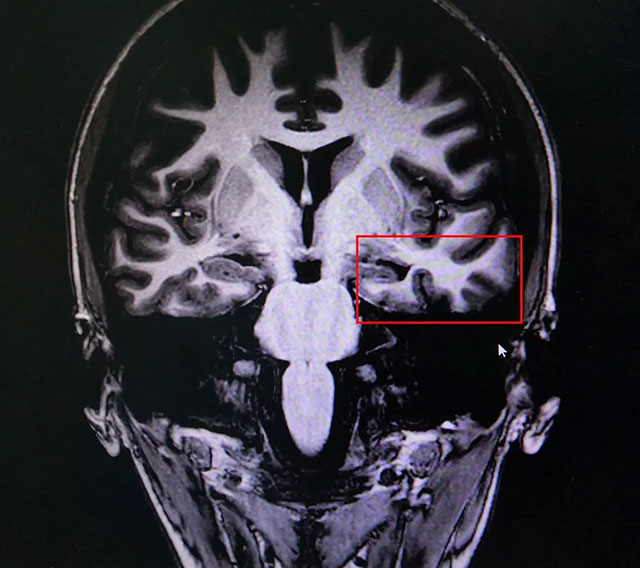

▲ 患者癫痫病灶区域

蓝十字脑科功能神经外科主任杨忠旭博士认真查看了雯雯各项检查报告并听取相关病情汇报后指出,一般幼时突发高热惊厥,尤其伴有抽筋的症状,会导致大脑缺血、缺氧,而海马对这种情况的耐受较差,极易造成其内的神经细胞受损,时间长了就会发展成海马硬化,成年后,有近一半以上的病人会因此患上顽固性癫痫。

雯雯癫痫诊断明确,系统内科药物治疗不佳,确诊为:难治性癫痫。应用现代神经影像学技术和电生理监测技术,能明确引起癫痫发作的的“责任病变”,手术指征明显,未见明显手术禁忌症。杨教授为她制定了周全的手术方案并做好充分准备。

3月28日,杨忠旭教授在助手杜立功协助下为患者进行了手术。术中,于颞中回、中部垂直穿刺,深部电极监测海马明显异常放电并有节律性改变,皮层电极监测提示颞极散在棘波,皮层与深部电极测试提示两者存在部分相互传导联系,皮层电极也有自发棘波产生。以外侧裂及labe静脉为主要解剖标志行左侧颞叶结构切除,先切除颞叶外侧,颞叶部分切除后颞窝、蝶顶窦、海马复合体完整暴露。而后切除海马头及海马体,术中见其海马体积缩小,质地较硬。切除后,再次脑电监测显示暴露脑区无异常放电,手术成功。